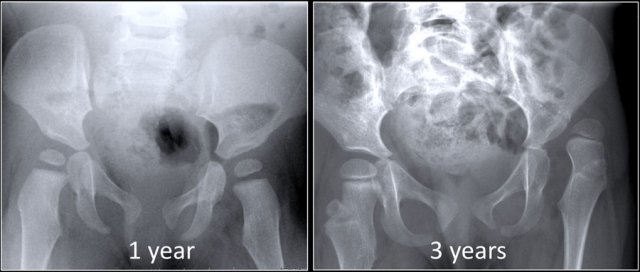

1. This is an AP and frog leg view of the pelvis belonging to the index patient.

demonstrating avascular necrosis of the left hip with <50% height loss of the lateral pillar of the femoral epiphysis

Compared to contralateral hip, there are

- Decreased size of femoral head

- Irregularity of femoral head

- Flattening of epiphyses

- Sclerotic appearance

- Central part of epiphyseal osific centre appears lucent/ fragmented, indicating fragmentation stage of the disease process.

- Lateral part height reduced but < 50%

If according to Herring’s lateral pillar classification - Group B

The lateral pillar is defined as the lateral portion of the femoral head, on the anteroposterior radiograph, that is demarcated from the central portion of the head by a lucent line of fragmentation.